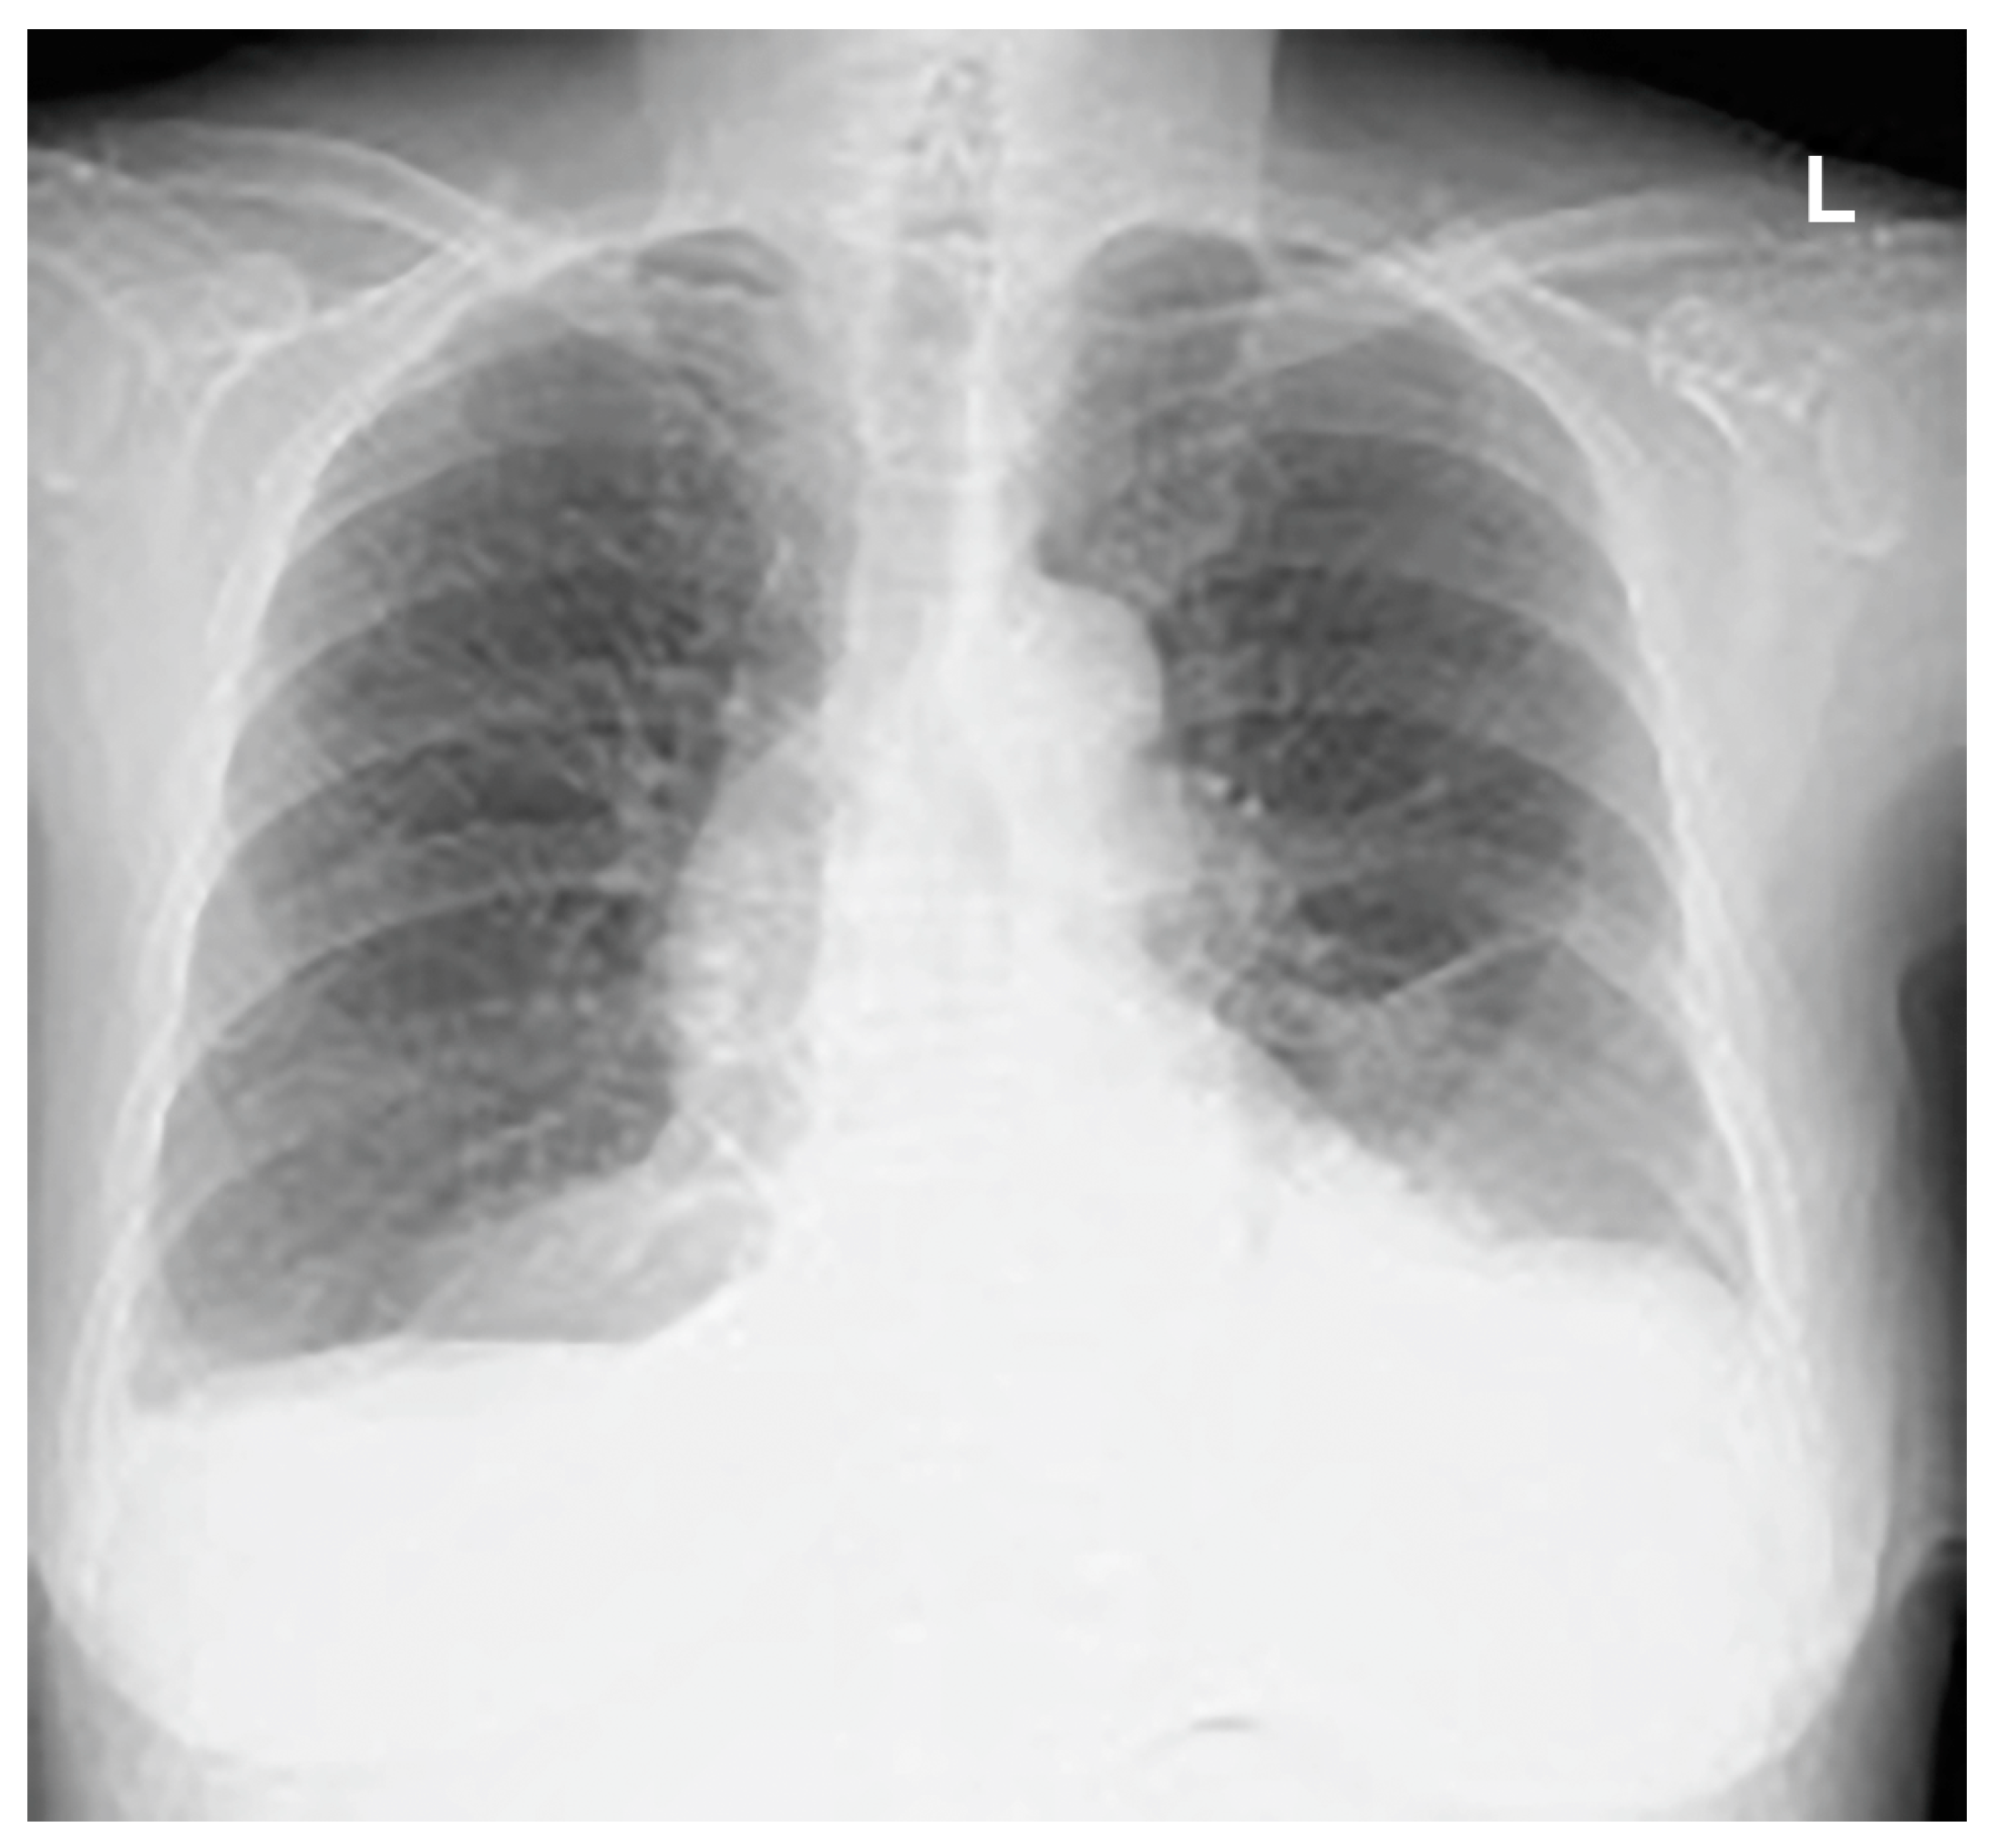

Thoracentesis and abdominocentesis were performed for detailed examination, and 1000 mL of each specimen was obtained. The cell block results of the obtained specimens indicated a suspected metastasis of high-grade serous carcinoma arising from the ovary. A biopsy under general anesthesia was scheduled to confirm ovarian cancer and to select drug therapy. However, after draining 1000 mL of pleural fluid, a large amount of left pleural fluid was still reaccumulated at the second examination two weeks later. Therefore, intubation under general anesthesia was judged to be high-risk. Therefore, the anesthesiologist requested the insertion of a left thoracic drain the day before. After the insertion of a thoracic drain, the patient was found to be COVID-19-positive on preoperative screening, and as a result, the patient’s biopsy surgery was postponed and the left thoracic drain was planned to be removed. However, considering that removing the drain immediately following insertion would be detrimental to the patient, removal was scheduled for the next day, to be followed by observation of the patient for several additional days. As planned, the drain was removed the day after insertion. However, approximately one hour following the drain’s removal, mediastinal and subcutaneous emphysema suddenly developed, with the patient also complaining of mild dyspnea. A left pneumothorax was then diagnosed using chest radiography. In addition, chest radiographic findings included mediastinal and subcutaneous emphysema observed in the anterior mediastinum and on the left side of the chest. Subsequently, a drain (20 Fr) was placed in the patient’s left thoracic cavity immediately after confirming the X-ray (Figure 2).

Figure 2.

Mediastinal and subcutaneous emphysema was observed in the anterior mediastinum and on the left sides of the chest, respectively.